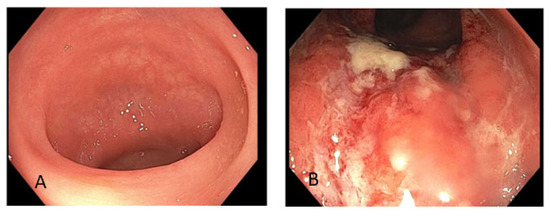

4.1. Case #1

4.2. Case #2